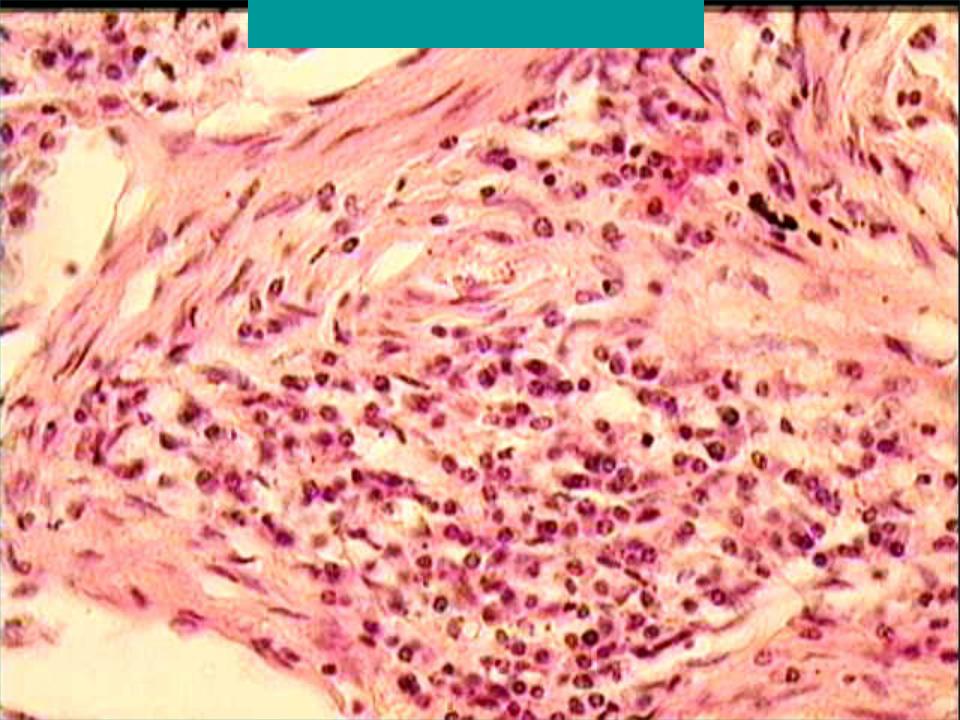

Карнификация Легкого: Микропрепараты и Диагностика

Раздел: Калейдоскоп образов